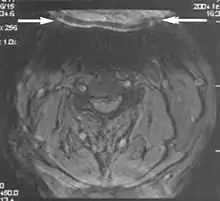

A wrap-around artifact also known as an aliasing artifact, is a result of mismapping of anatomy that lies outside the field of view but within the slice volume.[4] The selected field of view is smaller than the size of the imaged object. The anatomy is usually displaced to the opposite side of the image (Figs 6 and 7). It can be caused by non-linear gradients or by undersampling of the frequencies contained within the return signal.[1] The sampling rate must be twice the maximal frequency that occurs in the object (Nyquist sampling limit). If not, the Fourier transform will assign very low values to the frequency signals greater than the Nyquist limit. These frequencies will then ‘wrap around’ to the opposite side of the image, masquerading as low-frequency signals. In the frequency encode direction a filter can be applied to the acquired signal to eliminate frequencies greater than the Nyquist frequency. In the phase encode direction, artifacts can be reduced by an increasing number of phase encode steps (increased image time). For correction, a larger field of view may be chosen.[1]